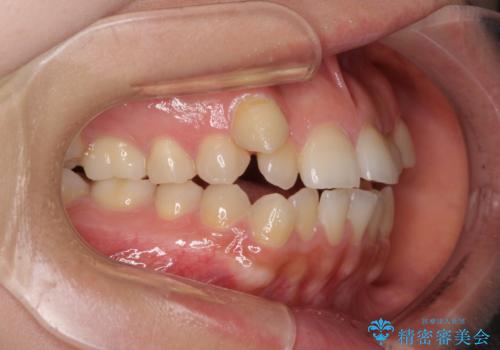

- 前歯のデコボコや八重歯、舌癖による開咬を気にして来院された患者様です。

目立たない装置を希望されたので、上顎が裏側装置のハーフリンガルを選択し、上顎小臼歯1本を抜歯して、補助装置を併用して矯正治療を行うこととしました。

補助装置を事前に使用したことで、あっという間に八重歯が改善し、ハーフリンガルにしては1年半もかからずに治療を終えることができました。